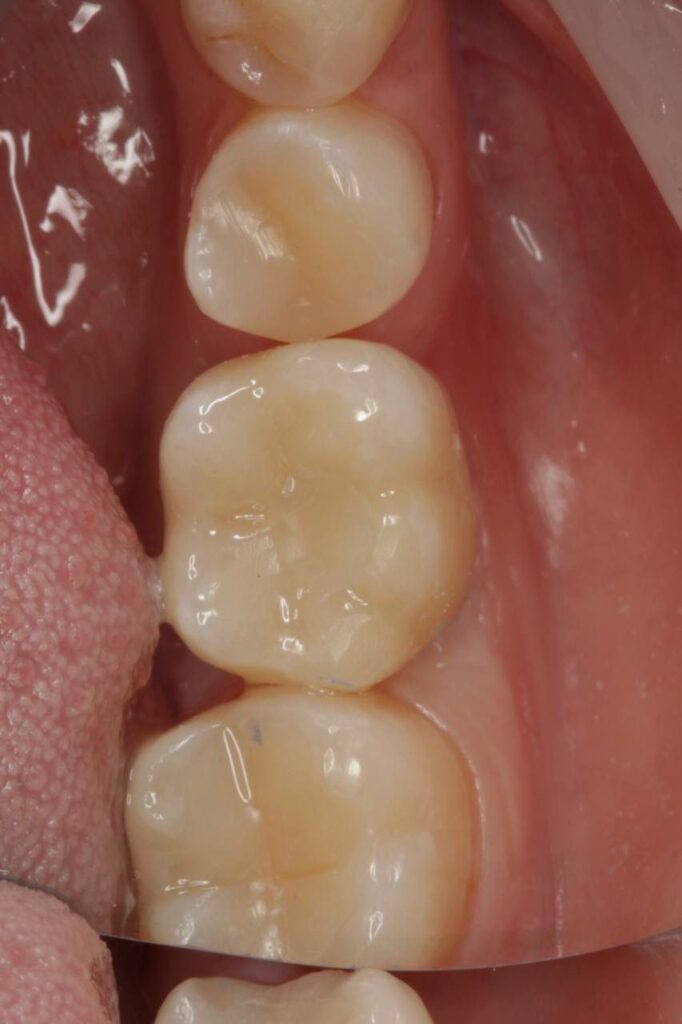

Специализация: терапия(эндодонтия), ортопедия, имплантология.